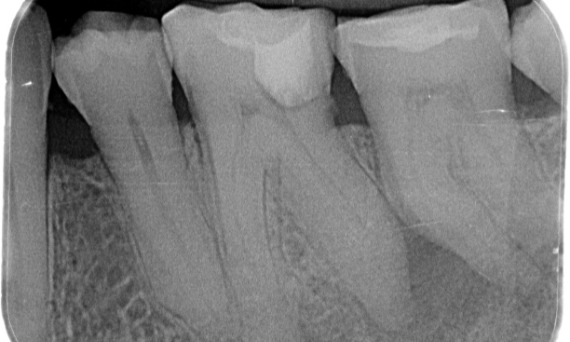

Un caso complejo con raíces largas y un sistema calcificado con un seguimiento de 14 meses

"Un éxito centrado en el paciente y el proceso". - Dr. Cowie

Antes: Radiolucencia periapical asociada principalmente con la raíz distal y pérdida de la lámina dura en la raíz mesial.

Después: En este caso, se eligió TruNatomy para permitir un enfoque apalancado en las caries y un enfoque en la conservación de la dentina pericervical, especialmente en el aspecto mesial donde el diente tuvo una restauración más mínima.

Dr. Jonathan Cowie (especialista en endodoncia)

Bath, Reino Unido